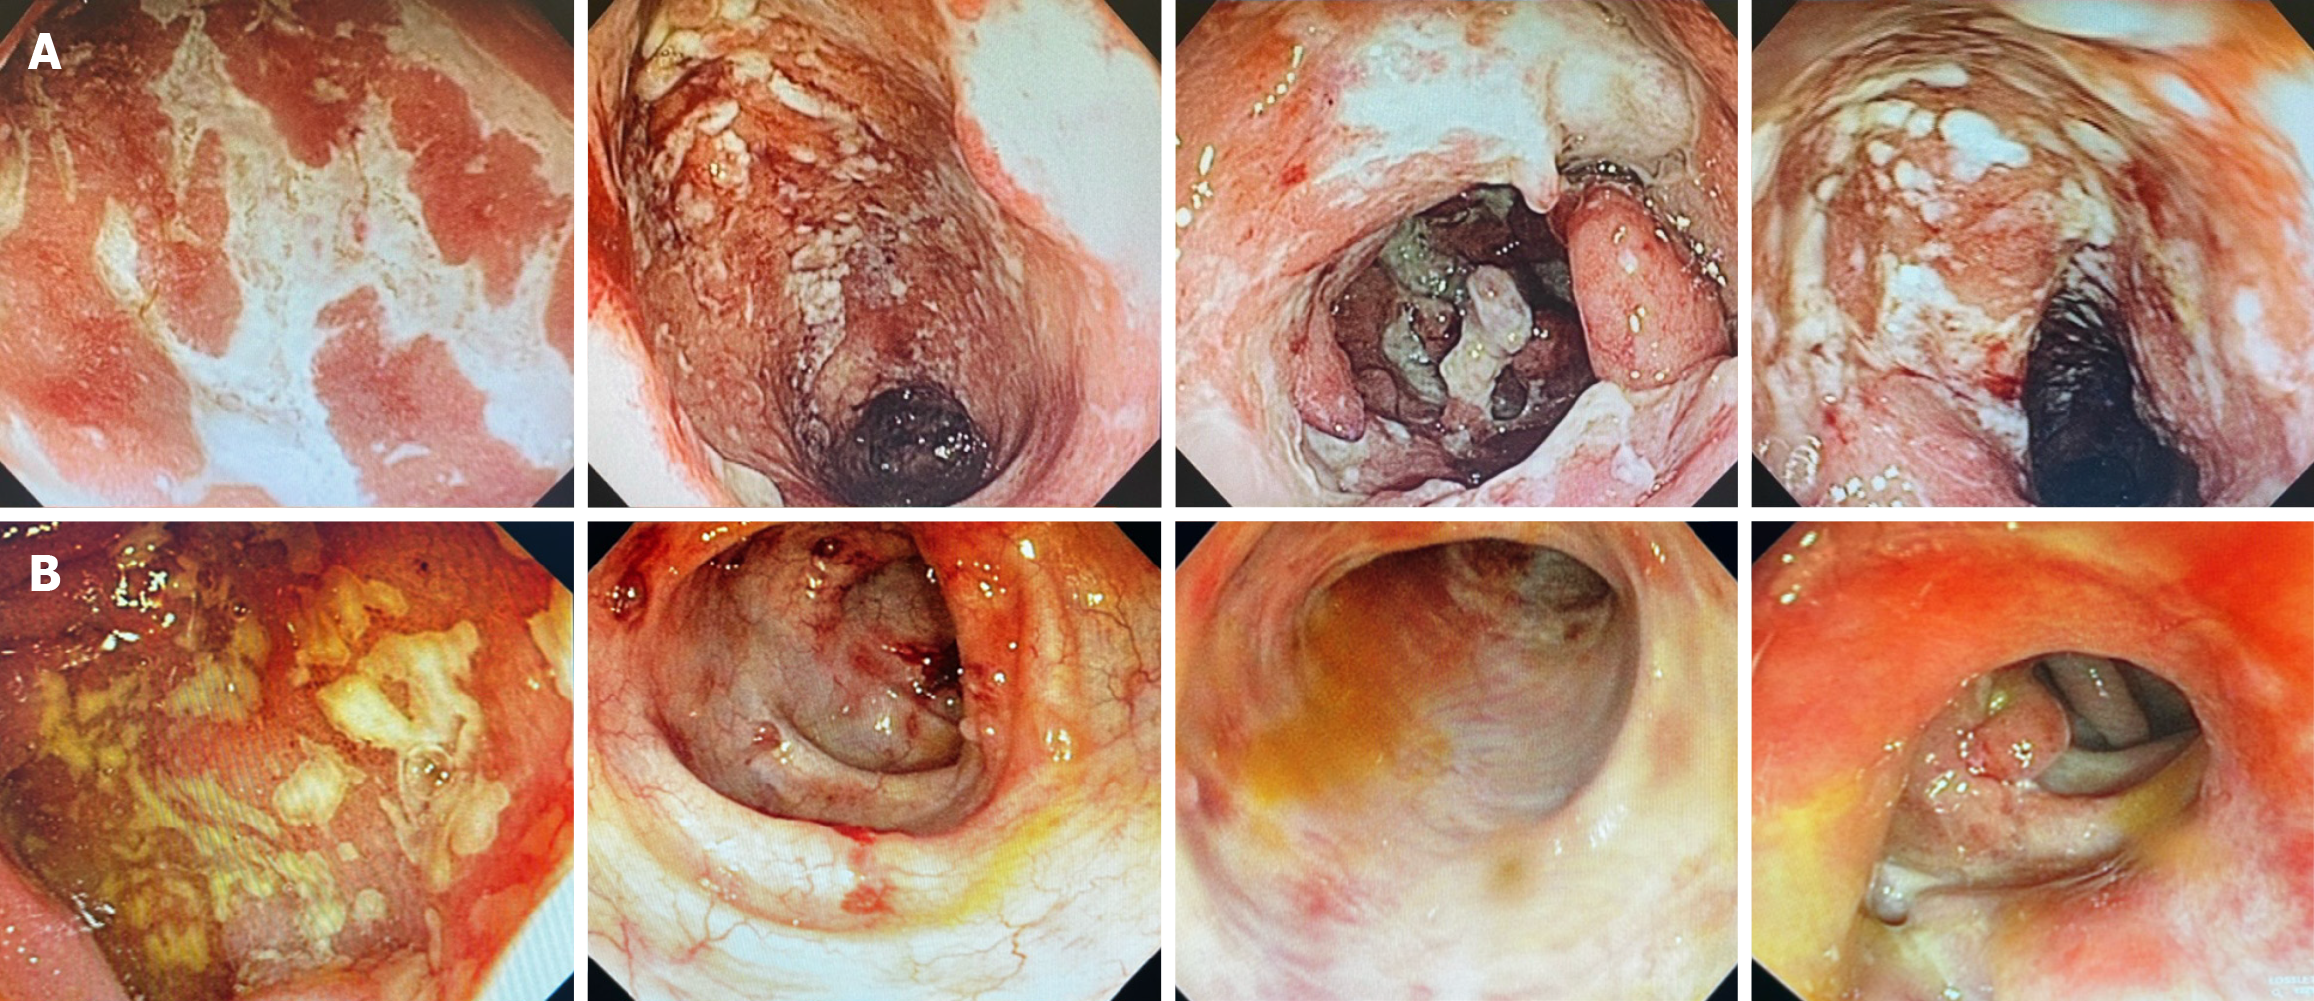

Figure 2 Colonoscopy.

A: Follow-up colonoscopy after vedolizumab therapy, demonstrating severe endoscopic activity of ulcerative colitis in the rectum (Mayo score: 3); B: Most recent colonoscopy showing severe endoscopic activity of ulcerative colitis involving the terminal ileum and other colonic segments (Mayo score: 3).